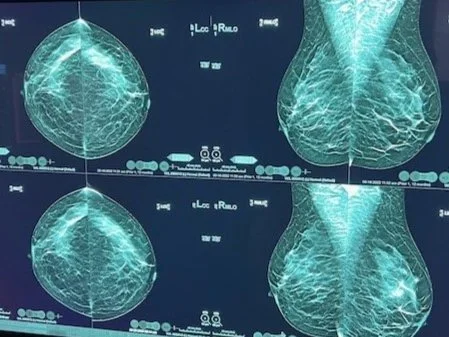

Siobhan Stofka BSN RN OCN 4/6/25 Siobhan Stofka BSN RN OCN 4/6/25 Why mammograms? Why are mammograms the gold standard for breast imaging? Read More